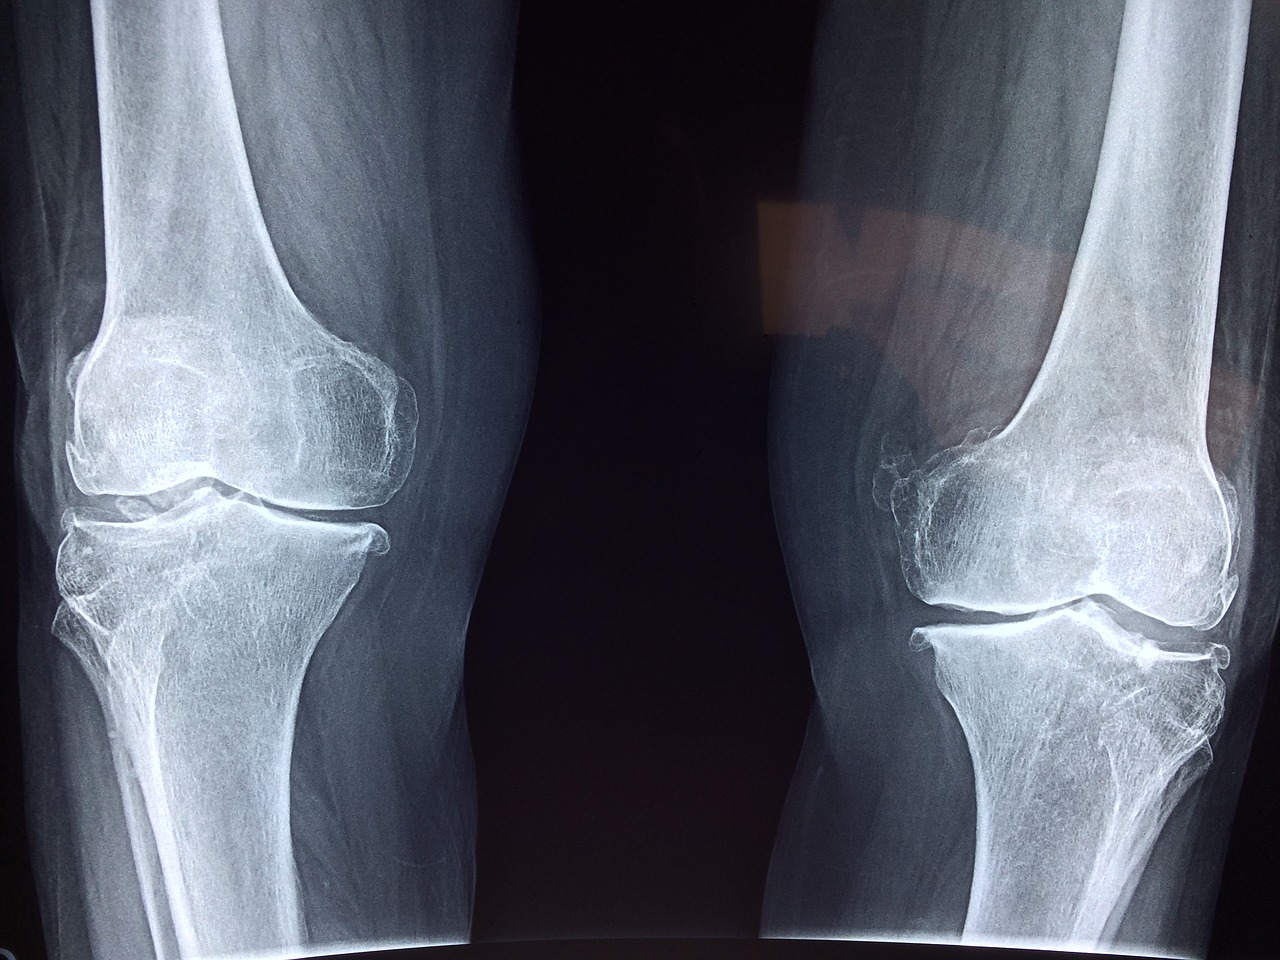

Ze ontdekten dat de leeftijd van kraakbeen grotendeels afhing van waar het zich in het lichaam bevond. Kraakbeen in enkels is jong, het is van middelbare leeftijd in de knie en oud in de heupen. Deze correlatie tussen de leeftijd van menselijk kraakbeen en zijn locatie in het lichaam stemt overeen met hoe ledematen herstel optreedt bij bepaalde dieren, die gemakkelijker regenereren aan de verste uiteinden, inclusief de uiteinden van benen of staarten.

De bevinding helpt ook te verklaren waarom verwondingen aan de knieën van mensen en, vooral, heupen lang duren om te herstellen en zich vaak ontwikkelen tot artritis, terwijl enkelblessures sneller genezen en minder vaak ernstig artritis worden.